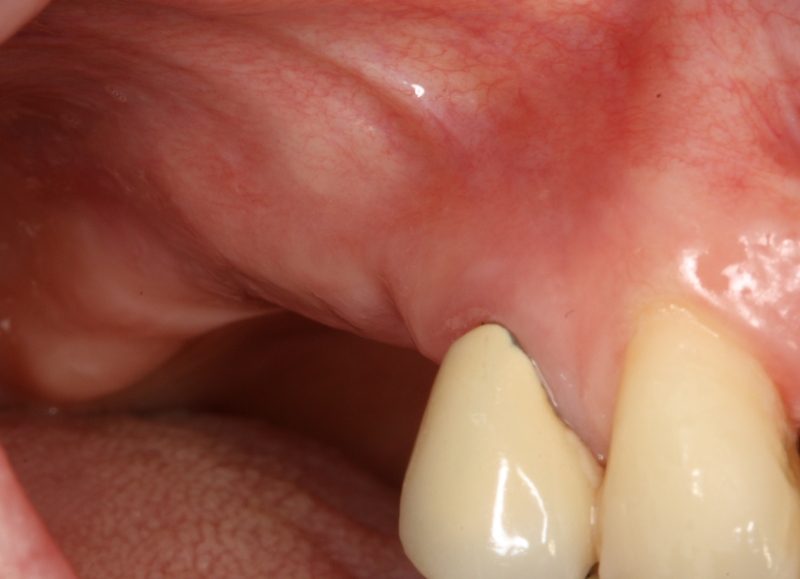

15/20 - Good soft tissue situation after healingGBR with maxresorb® & Jason® membrane - Prof. Dr. Dr. D. Rothamel

-